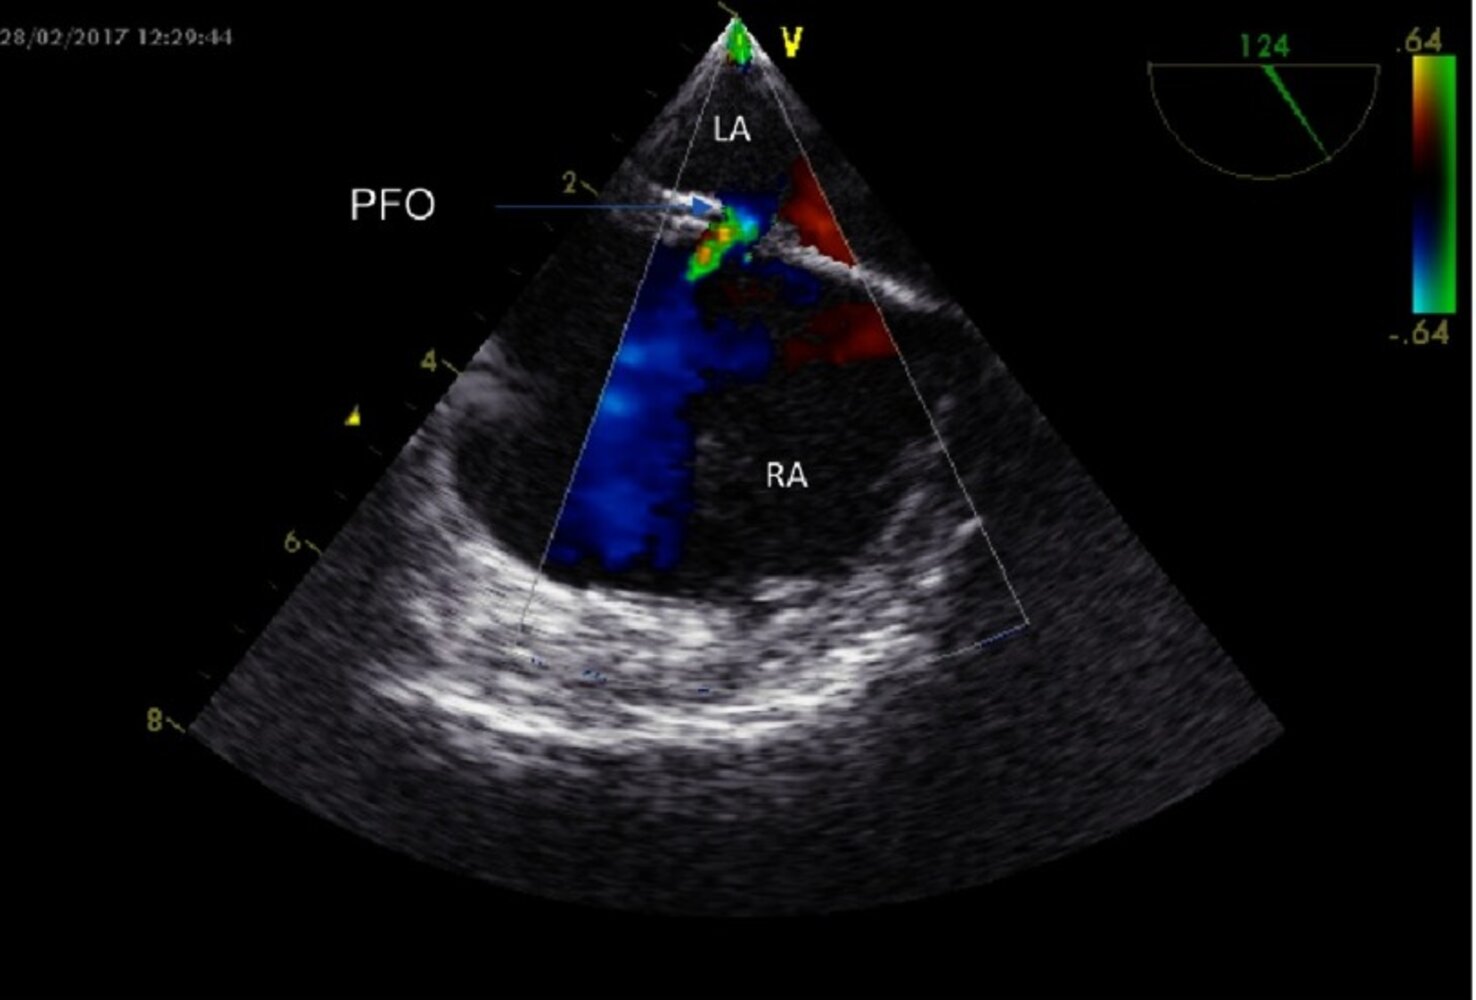

Diagnostics [39]

-

General principles

- Diagnosis of a PFO is frequently incidental (e.g., during PCI or cardiac surgery).

- Diagnostic studies are requested as a part of the assessment of conditions suggestive of PFO, e.g., cryptogenic stroke.

TTE with agitated saline (best initial study)

- Right-to-left shunt that increases with the Valsalva maneuver and coughing

- Other findings: atrial septal aneurysm [40]

TEE with agitated saline (most sensitive test) may be considered if:

- TTE is inconclusive

- There is a high index of suspicion for PFO despite negative TTE

- PFO anatomical assessment is needed after positive TTE